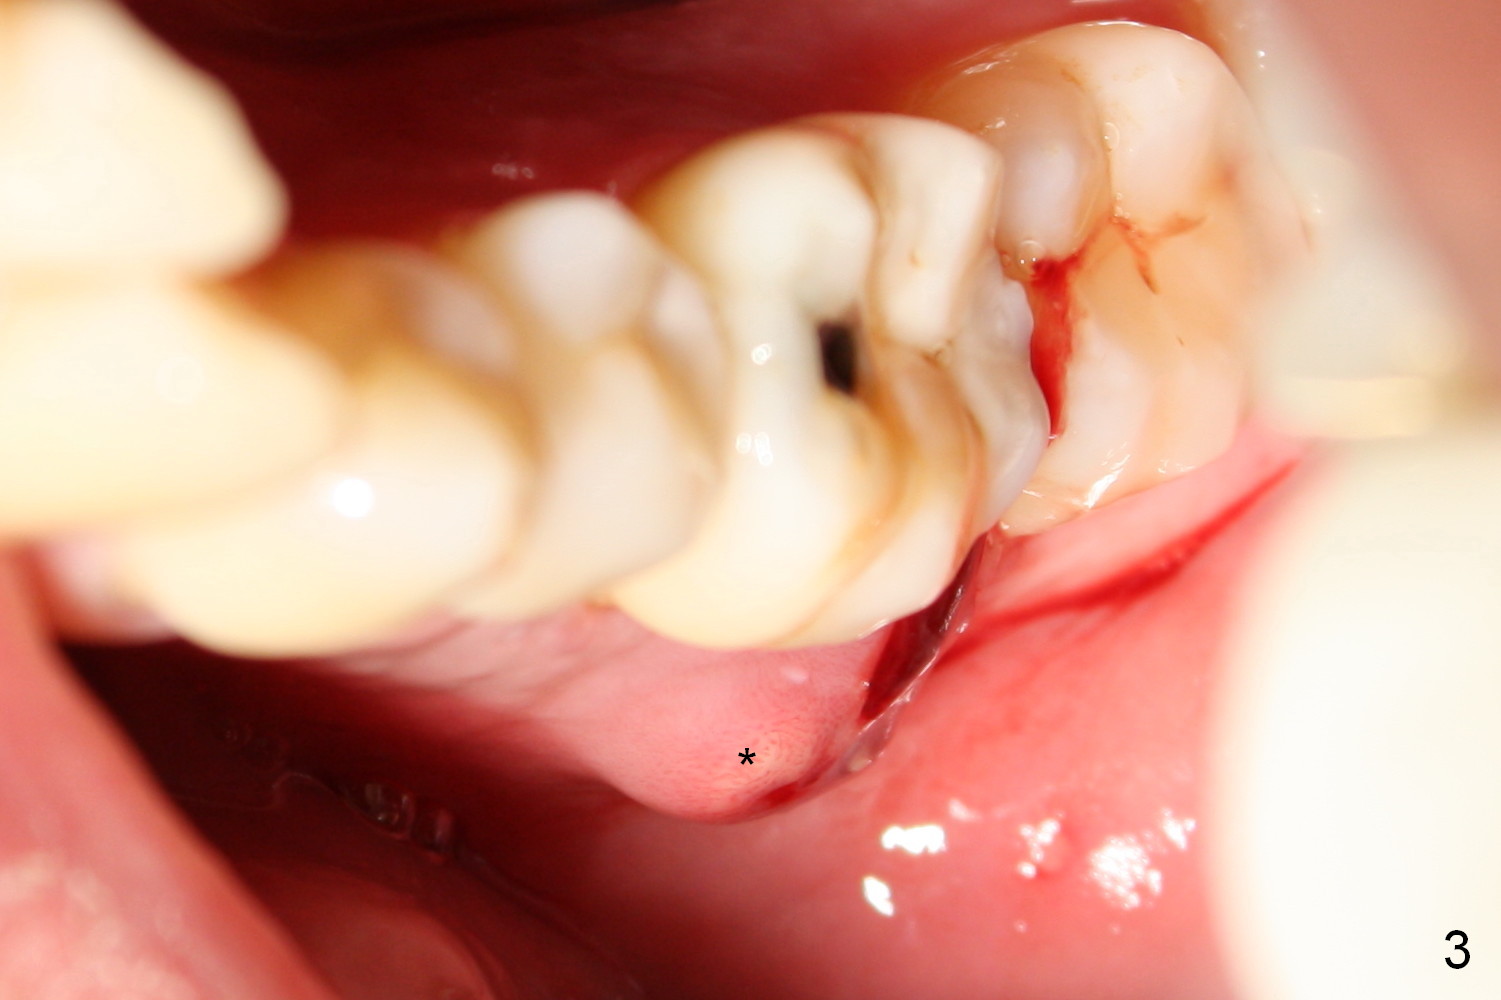

The mesial and distal crests of the tooth #19 were even for a 50-year-old man 7 years ago. Three years later, swelling developed around the distal root with bone loss (Fig.2 *). Three months later, localized swelling occurred (Fig.3 *) with oozing. The patient had thrombopenia (platelet 40 K). The tooth was extracted with suture. There is distolingual root tip resorption. Two months and a half later (Fig.4), a 6x17 mm implant was placed (Fig.5). The implant osteointegrated 5 months postop (Fig.6). The distal crest re-appears 5 months (Fig.7), 2 years (Fig.8) and 2 years 8 months (Fig.10) post cementation. At the last appointment, the patient complained of pain and swelling at #30 with mesial bone loss (Fig.10 *), as compared to Fig.9 taken 9 years ago. The mesiolingual pocket is deep. After scaling and Chlorhexidine irrigation, Arestin is locally administered.

It appears that the lower molars have a type of occlusal trauma. There is anterior open bite (Fig.10 double arrows).